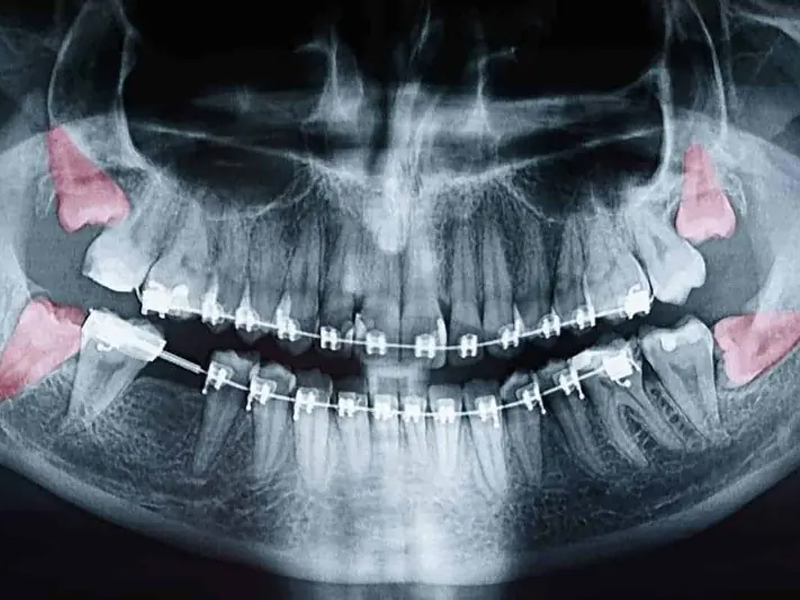

Медична статистика свідчить, що від 10% до 41% населення планети мають вроджену відсутність хоча б одного зуба мудрості, що називається агенезією. На цей процес впливає спадковість, стать (у жінок зуби мудрості відсутні дещо частіше) та навіть етнічне походження. Цікаво, що у багатьох людей зачатки зубів існують, але залишаються ретинованими — тобто прихованими під яснами, що часто потребує рентгенологічного контролю.

Наявність зубів мудрості не є автоматичним показанням до операції. Якщо вони прорізалися рівно, не травмують слизову оболонку та не тиснуть на сусідні зуби, їх можна зберігати протягом усього життя. Проте стоматологи наполягають на видаленні в разі виникнення хронічного запалення, карієсу, зміщення зубного ряду або утворення кіст навколо ретинованого зуба.